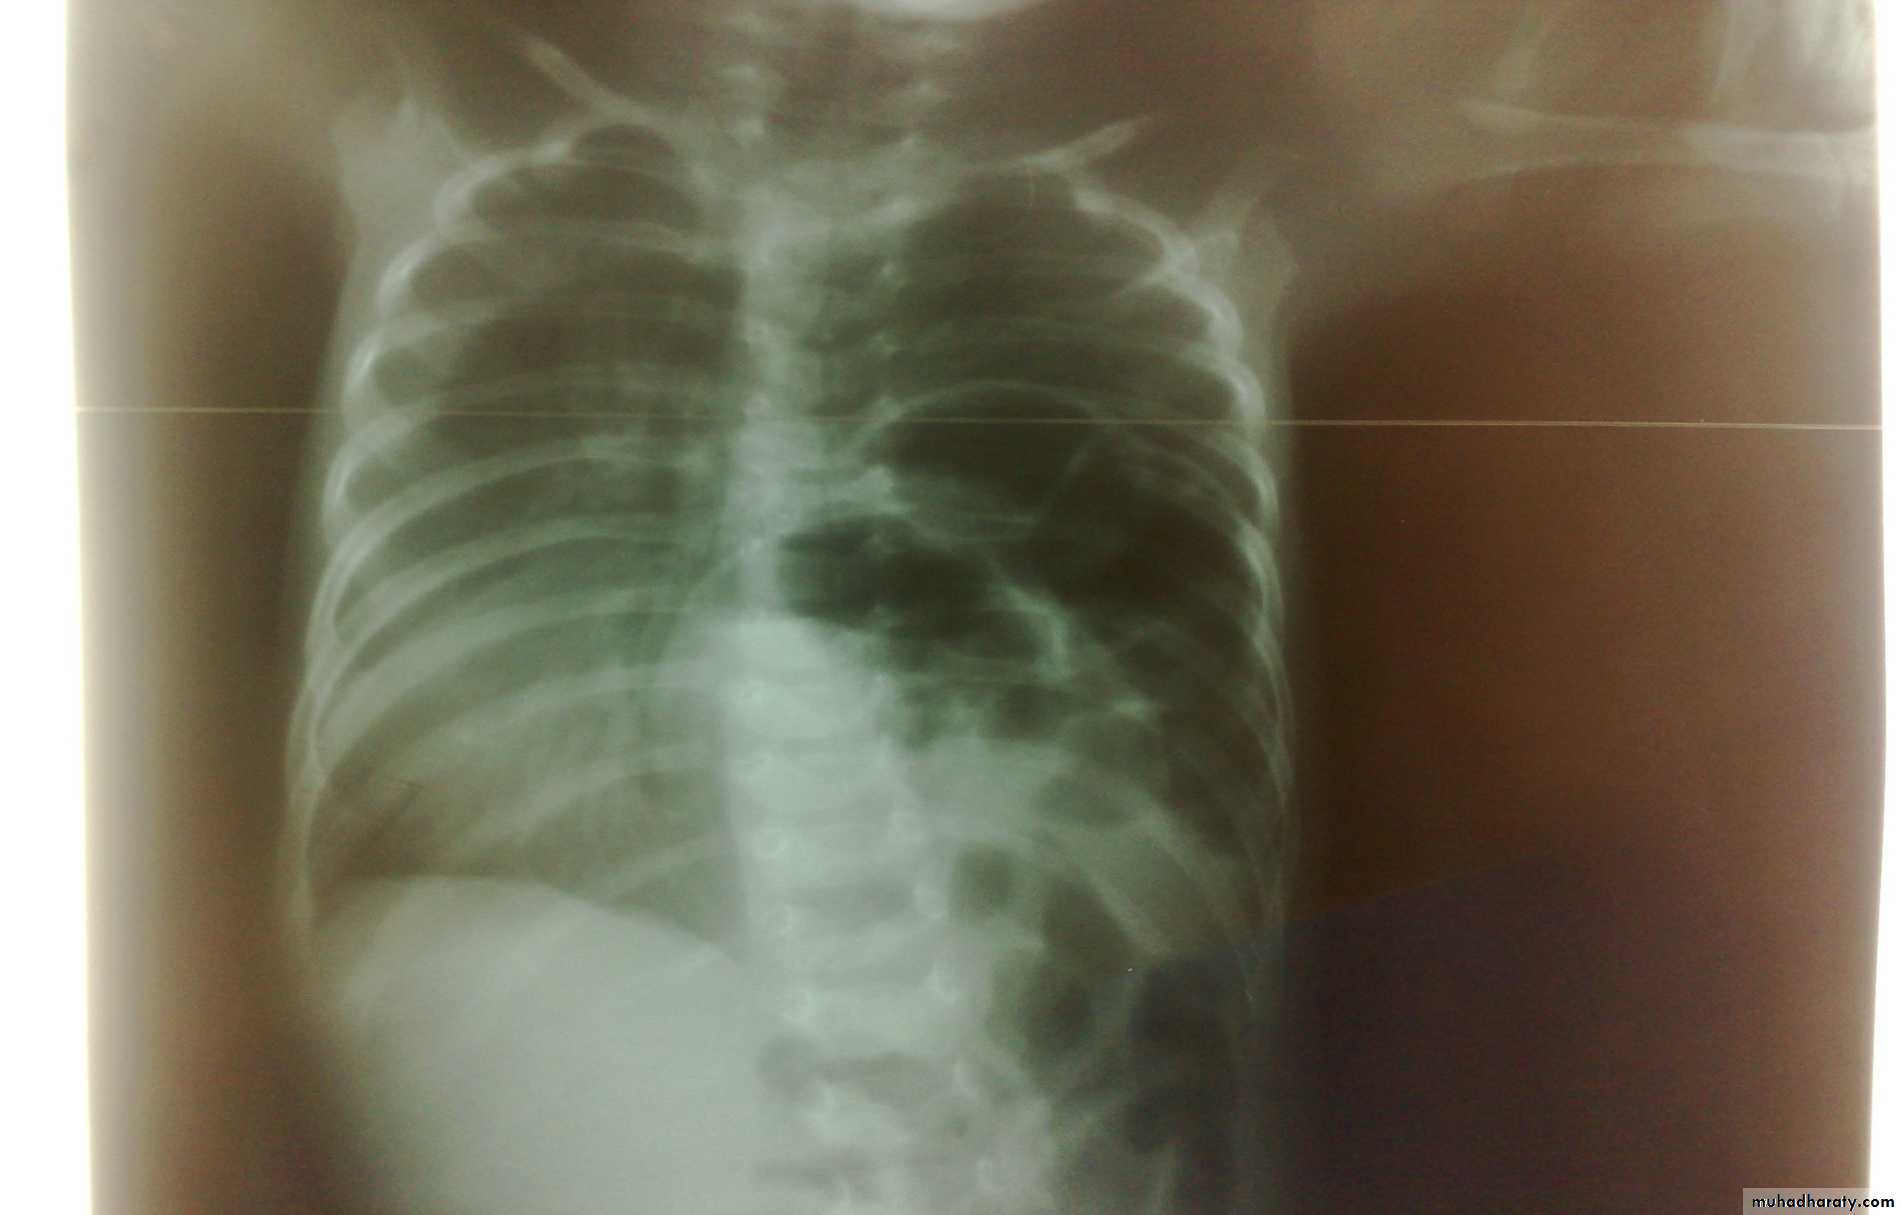

Diaphragmatic eventration

plication